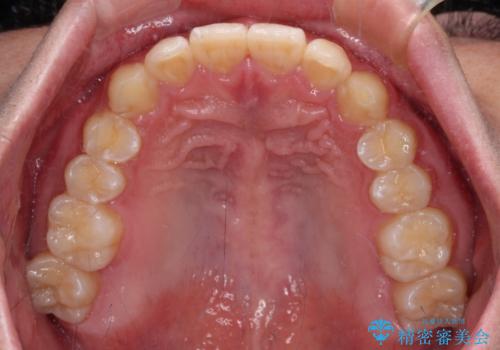

- 前方に傾斜した前歯を気にして来院された患者様です。

強く食いしばってしまう癖があり、下顎前歯に押し出されて上顎前歯が前方へ斜めに突き出している状態でした。

IPR(歯と歯の間を削る)を多用して、インビザラインにて矯正治療を行うこととしました。

口元を引っ込めるためのゴムかけを頑張っていただき、満足のいく上顎前歯の傾斜へ改善することができました。